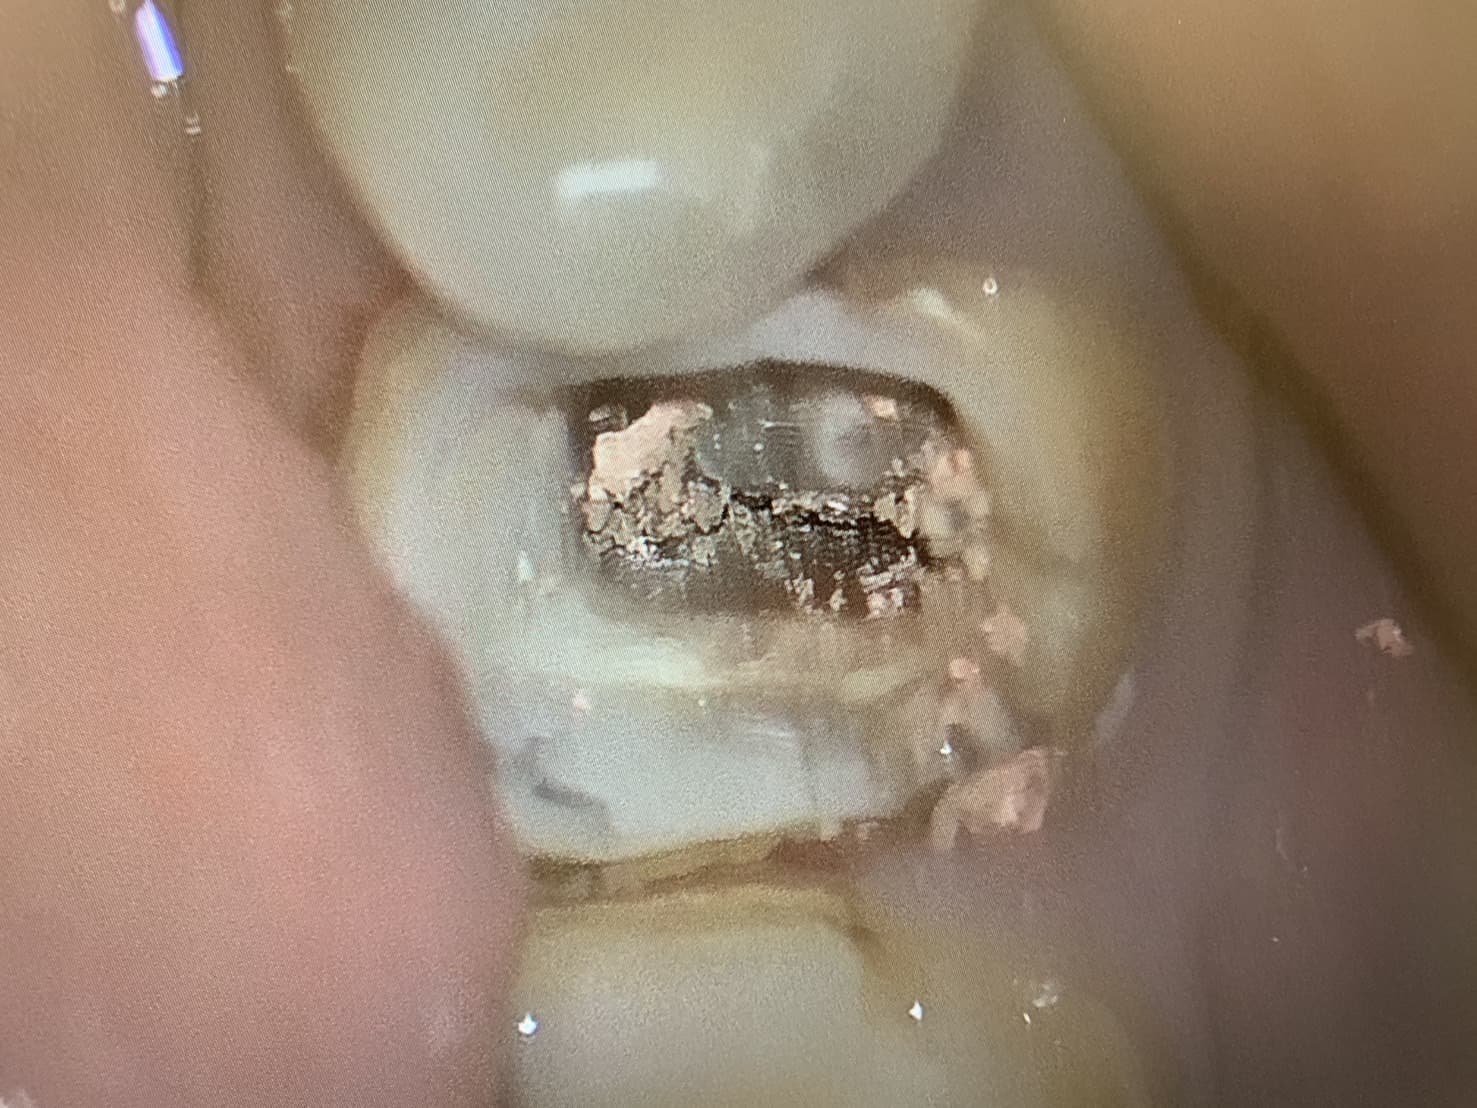

マイクロスコープを使用し「肉眼では見えないほど小さな根管(神経が通っている歯の中の管)も確認しながら行う根管治療です。

「精密根管治療」「マイクロエンド」とも呼ばれます。

マイクロスコープを利用し、根管内を直視して治療する精密根管治療は他院で抜歯と言われた歯でもできる限り残せる可能性があります。

むし歯治療では肉眼では確認できないほど小さなむし歯を発見したり、健全な歯質を最大限残したりするためにマイクロスコープが活用されています。

また、むし歯を削ったあとの歯の修復作業でもマイクロスコープを使うことで、天然の歯と詰め物・被せ物との境目を最小限に抑えることができます。